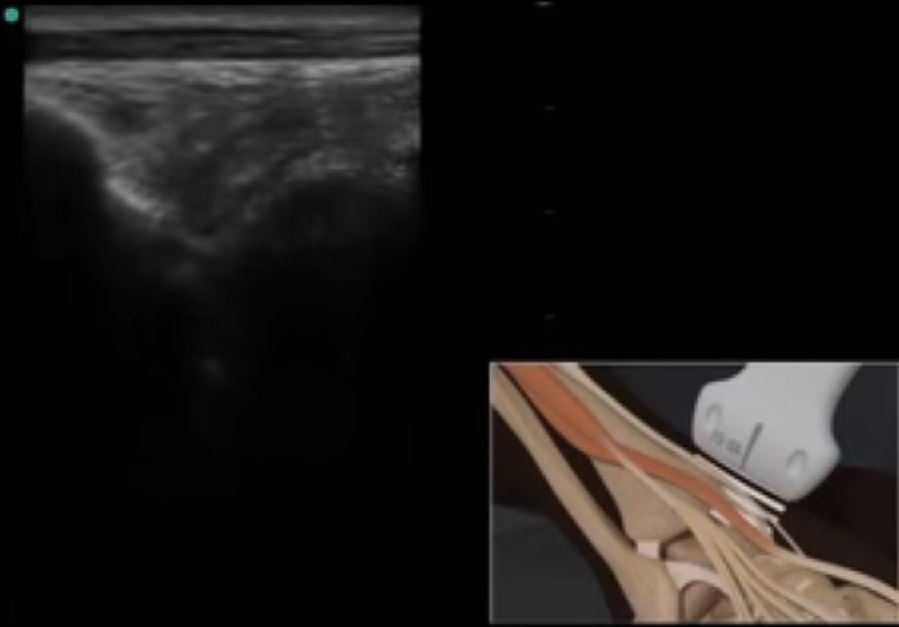

Imagen de la posición del transductor en el tendón tibial anterior en el pie y el tobillo